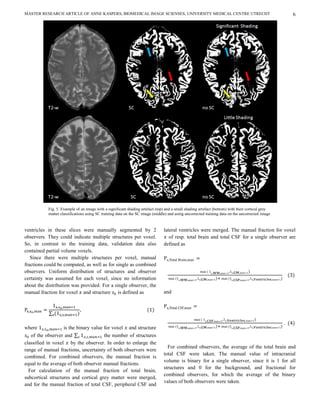

Routine choices                                                                cortical grey matter classification is shown in figure 5 for a

participant scan with little and one with significant shading.

In this study, volume measurements of subcortical                             After correction, cortical grey matter was better classified on

Fig. 5. Example of an image with a significant shading artefact (top) and a small shading artefact (bottom) with their cortical grey

matter classifications using SC training data on the SC image (middle) and using uncorrected training data on the uncorrected image

(right).